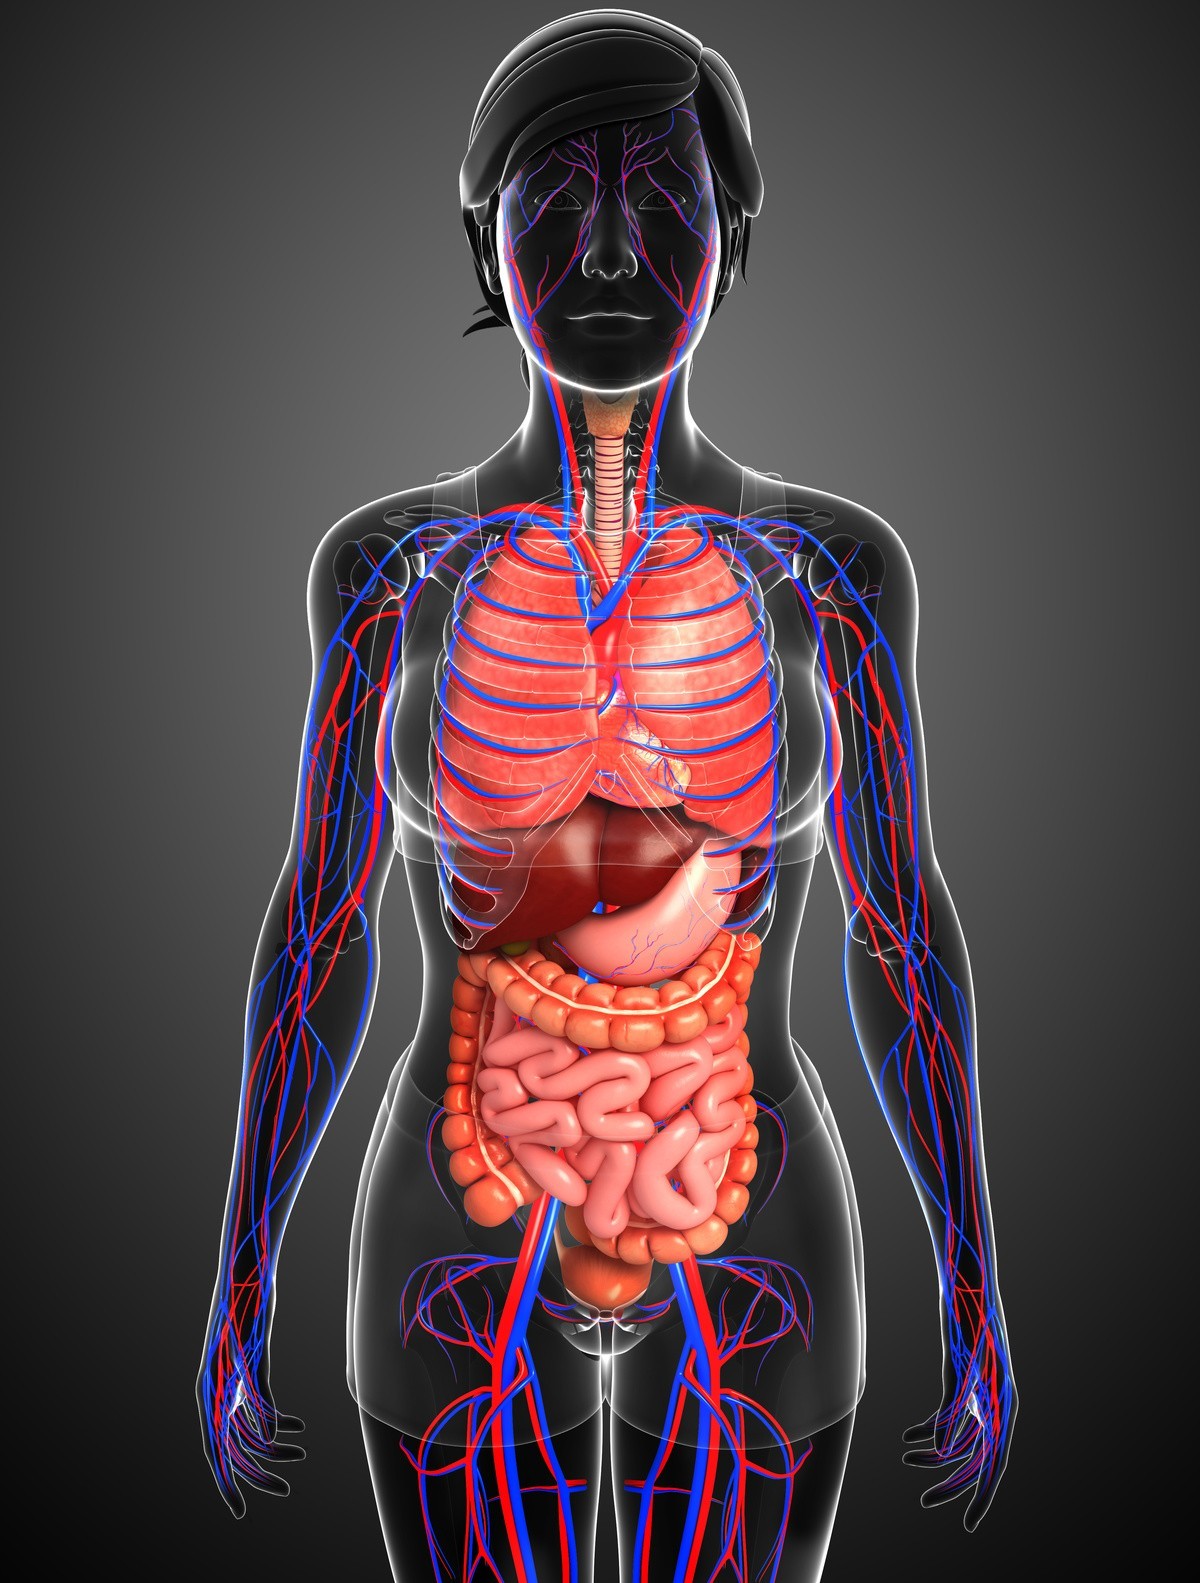

Анатомия человека: кровеносная система и её связь со скелетом